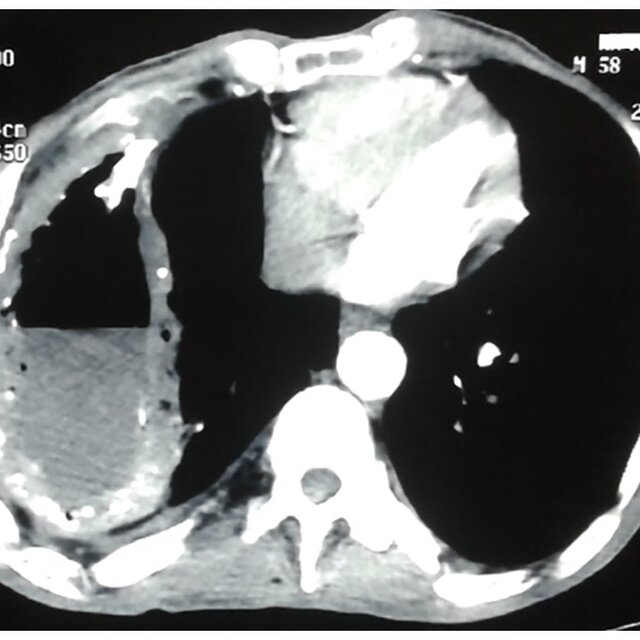

Accumulo di pus all'interno di una cavità, anche se il termine è più spesso applicato al versamento purulento all'interno del cavo pleurico (Empiema pleurico). La condizione può essere certamente paragonata ad un ascesso ed i sintomi che lo contraddistinguono sono Dolore, Febbre, difficoltà respiratoria. L'evenienza è di una gravità spesso elevata ed il trattamento consiste nel drenaggio del versamento nel più breve tempo possibile.

L'empiema pleurico si rinviene spesso nella Polmonite, nelle Tubercolosi polmonari e nelle ferite penetranti del Torace.